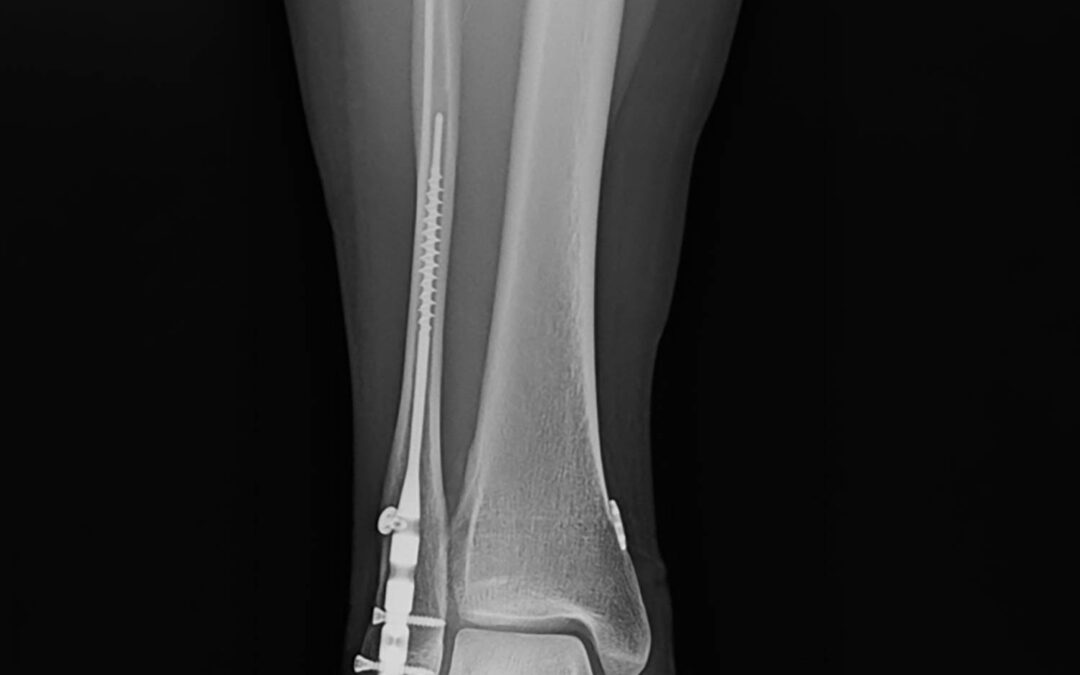

The transition from traditional Open Reduction Internal Fixation (ORIF) with plates and screws toward intramedullary fibular nailing represents a significant paradigm shift in ankle fracture management. While historically reserved for “train wreck” patients–those with compromised soft tissue, diabetes, or advanced age–current clinical evidence suggests that fibular nails are highly effective for simpler fracture patterns, such as stress-positive Weber B fractures.

- Modern Primary Indications: Simple, stress-positive Weber B fibular fractures. These patients benefit from minimally invasive surgery (MIS), zero hardware prominence, and small incisions.

Surgical Technique and Reduction Strategies

A common misconception is that the nail itself achieves the reduction. Experts emphasize that the surgeon must reduce the fracture before or during nail insertion.

Radiographic vs. Functional Outcomes

The study utilized the McLennan and Ungersma guidelines to qualify reductions as “good,” “fair,” or “poor.”

- Reduction Accuracy: 97% of cases were reduced to length; 100% achieved closure of the medial clear space.

- Acceptable Displacement: Approximately 9% of cases showed “fair” reduction, often involving a 1–2 mm posterior displacement. This is frequently due to the syndesmotic screw/button passing through the fracture site.

- Clinical Relevance: There is no documented clinical difference in functional outcomes between “good” and “fair” radiographic reductions. Because the fibula is largely extra-articular, a “functional reduction” (restoring gross anatomy, length, and rotation) is sufficient for patient satisfaction and long-term success.